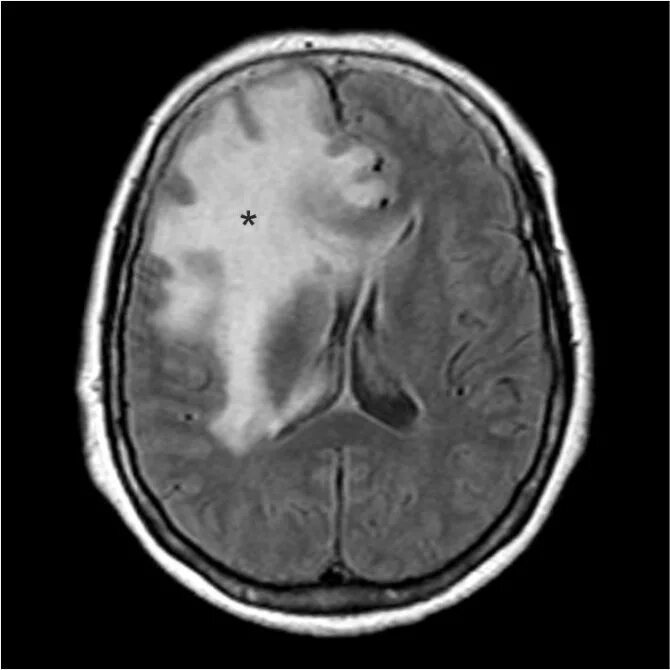

Отек головного мозга мрт